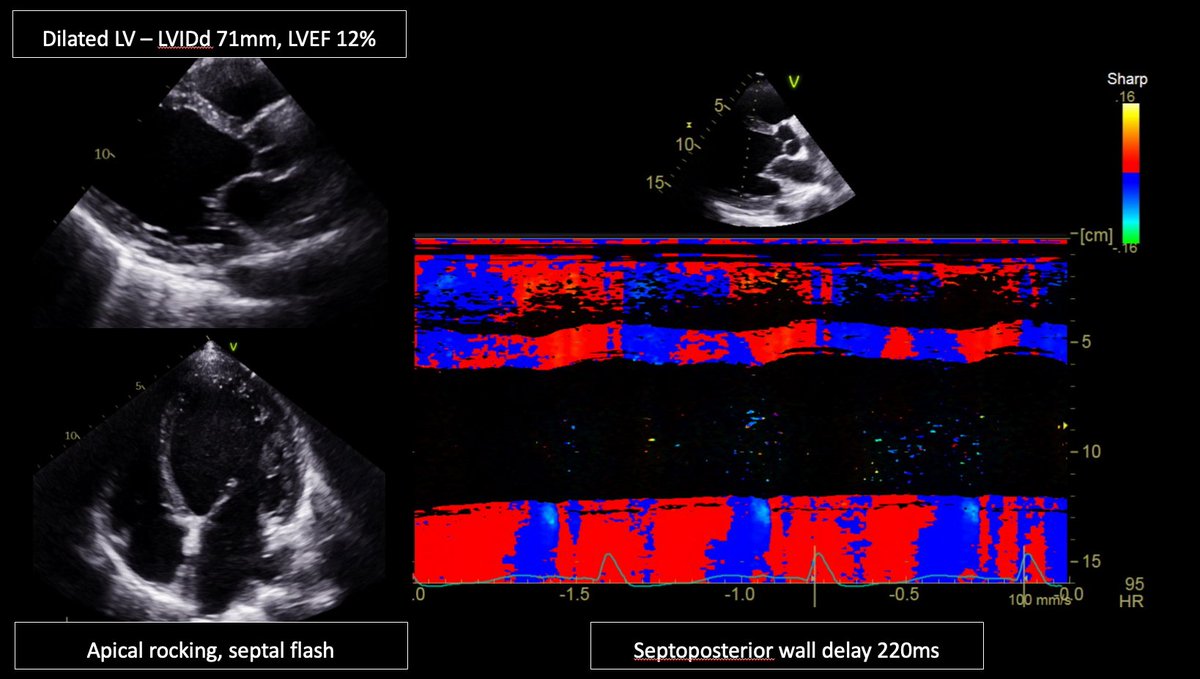

1/ I wonder what #Epeeps would do for a 62yo male patient with NICMP, LBBB QRSd >200ms, LVIDd 71mm, LVEF12%? Conventional CRT, LBB-CRT, LOT-CRT, too advanced for CRT? For CRT, any vendor preferences? @finnakerstrom @James_Elliott01 @enes_elvin @riley_guntrip @chris_monkhouse